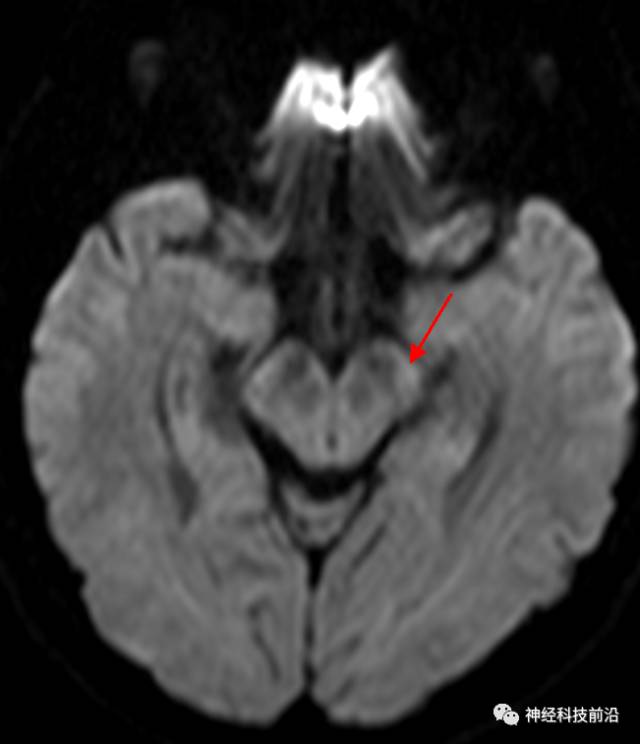

皮质脑桥束与脑干高信号(黄色)纤维束

脑干内高信号为一近环形纤维束,其作用尚待研究。

终上所述:脑干高信号为一近环形纤维束,内囊后肢高信号为皮质脑桥束,皮质脊髓束在中脑位置略靠后。高信号位于中脑前缘,是皮质脑桥束的位置所在,另外有部分桥连纤维。